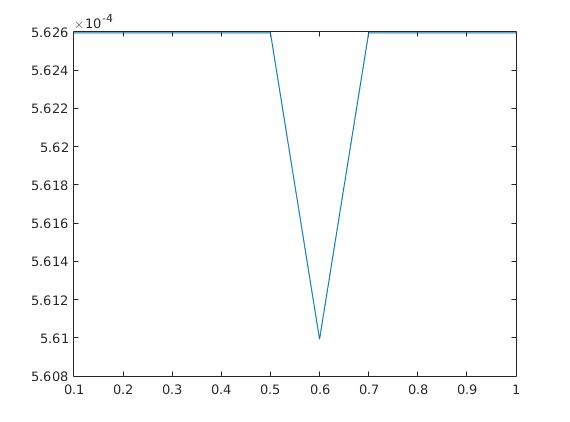

The parameters , and were optimized by comparing the final results with the existing ground truth in both cases. Here we mention that the choice of parameters is not a trivial task, since the result strongly varies with a change in the parameters. In figure 5, the scaling between the error in the -norm between exact and reconstructed image sequence per pixel per time step and the choice of each parameter out of a certain range is displayed examplarily for the heart data set. Here, we chose , and and kept two parameters fixed while plotting the error in the third one. The adaption of parameters in case of real data and, if possible, the elimination of some of them remains a future task.